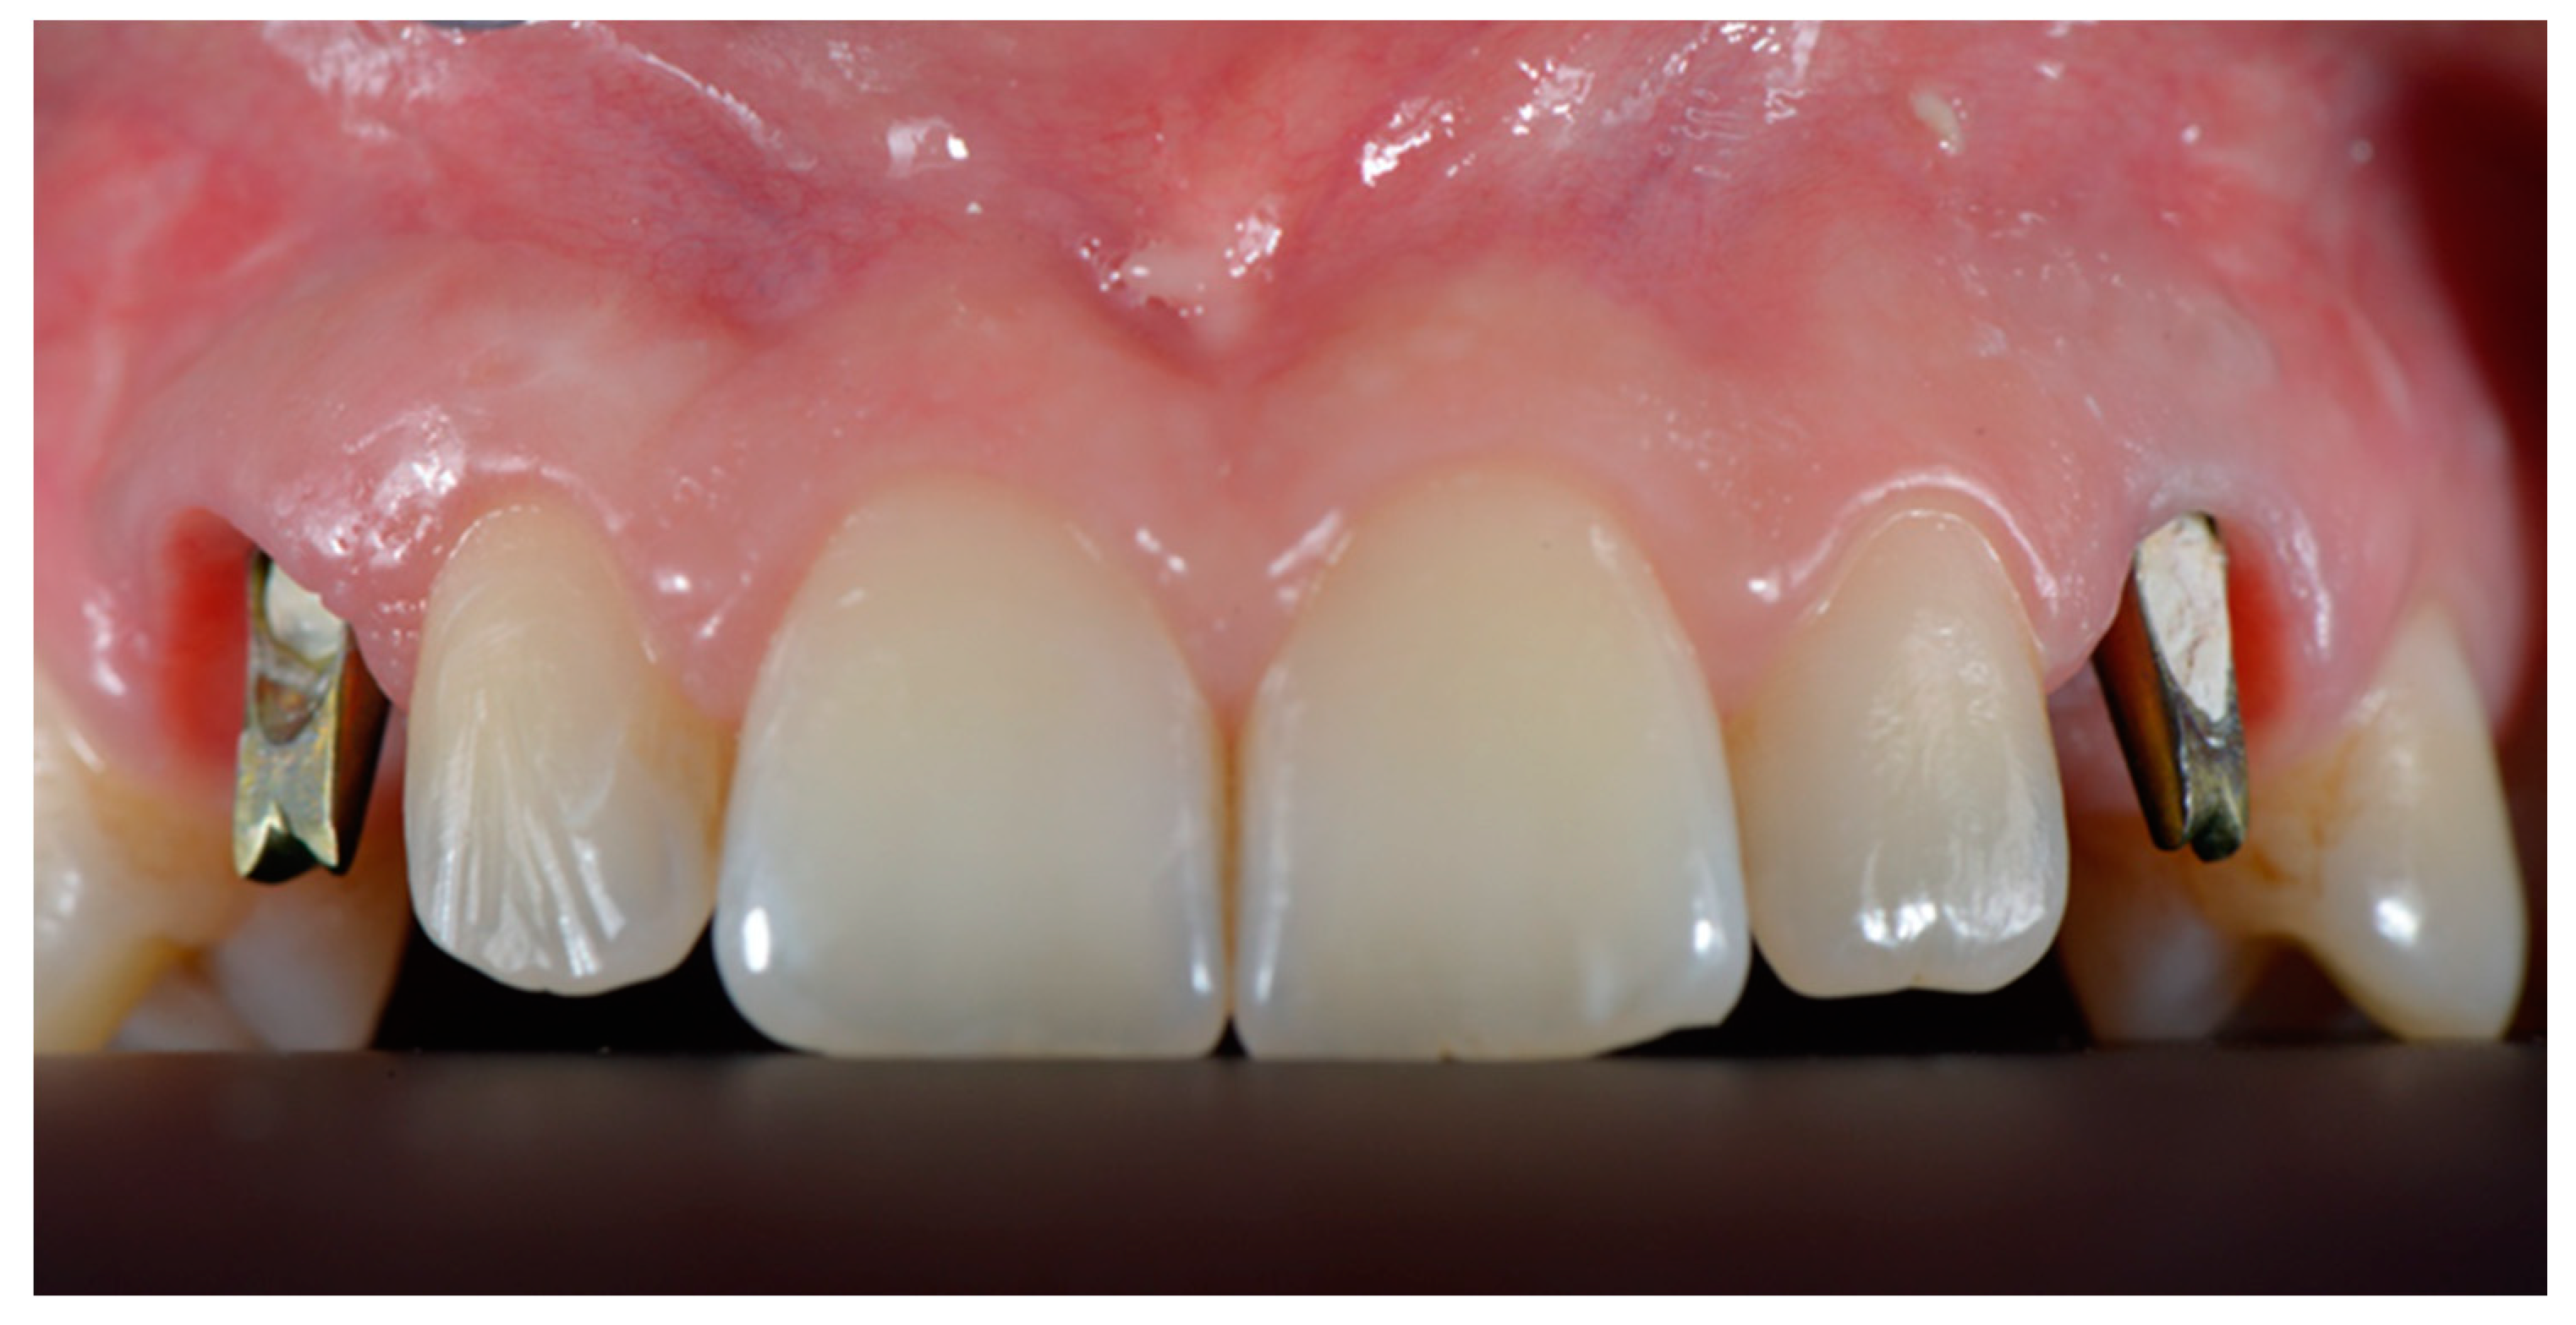

2.3. Surgical and Prosthetic Workflow

2.4. Outcome